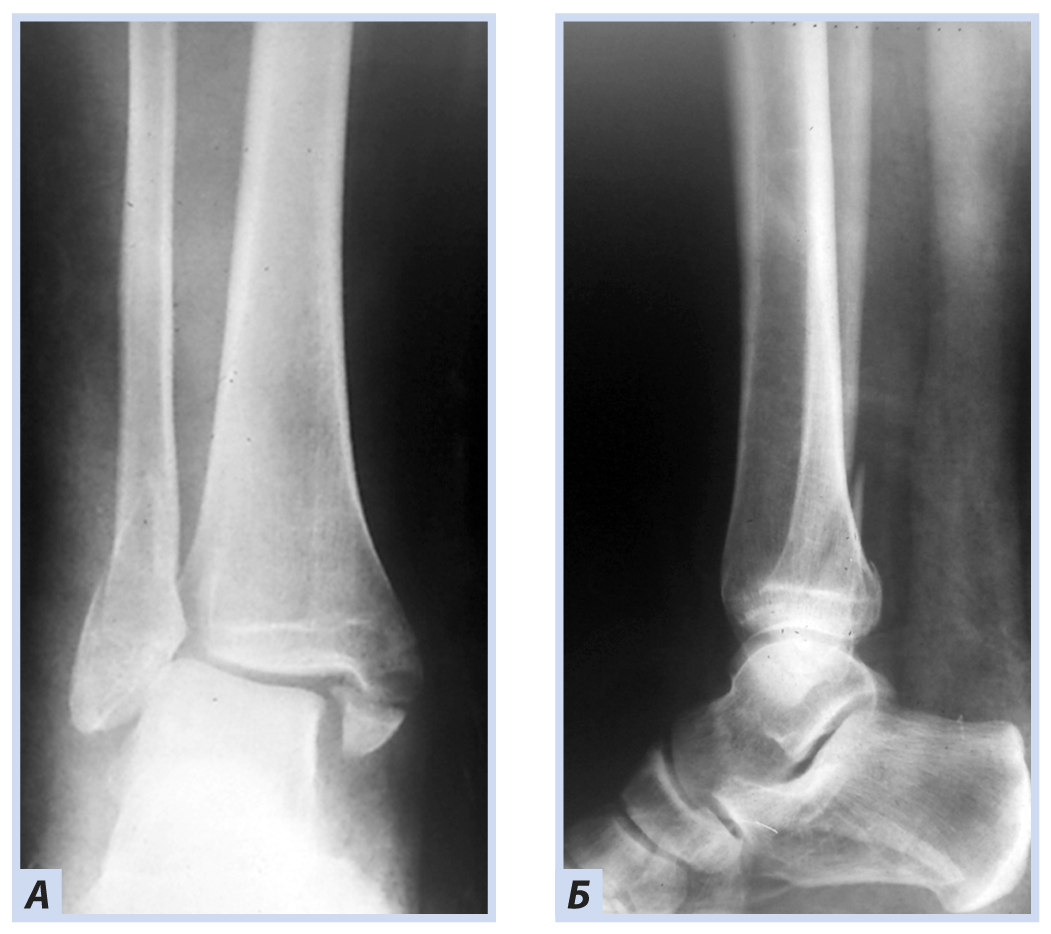

Девочка, 13 лет, диагноз: «Закрытый дистальный остеоэпифизеолиз левой большеберцовой кости, Salter–Harris III тип, Tillaux fractures». Травму получила, упав со скейтборда. По механизму травмы — супинационно-эверсионный перелом. Учитывая внутрисуставной характер перелома, остеосинтез выполнен с открытой репозицией и фиксацией отломков перекрещивающимися спицами. Дополнительная иммобилизация осуществлялась в задней гипсовой лонгете до коленного сустава. Контрольные рентгенограммы выполняли через 6 и 8 нед. после репозиции. Спицы удалены через 8 нед., конфигурация сустава восстановлена полностью (рис. 6–9).

Рис. 6. Девочка, 13 лет. Рентгенограммы дистального отдела костей левой голени. Остеоэпифизелиз дистального отдела левой большеберцовой кости Salter–Harris, III тип, Tillaux fractures: А — прямая проекция; Б — боковая проекция.

Рис. 7. Тот же пациент. Рентгенограммы дистального отдела костей левой голени. Остеосинтез перекрещивающимися спицами: А — прямая проекция; Б — боковая проекция.

Рис. 8. Тот же пациент. Рентгенограммы дистального отдела костей левой голени через 6 нед. Консолидация костных отломков: А — прямая проекция; Б — боковая проекция.

Рис. 9. Тот же пациент. Рентгенограммы дистального отдела костей левой голени через 8 нед. Консолидация костных отломков. Спицы удалены: А — прямая проекция; Б — боковая проекция.